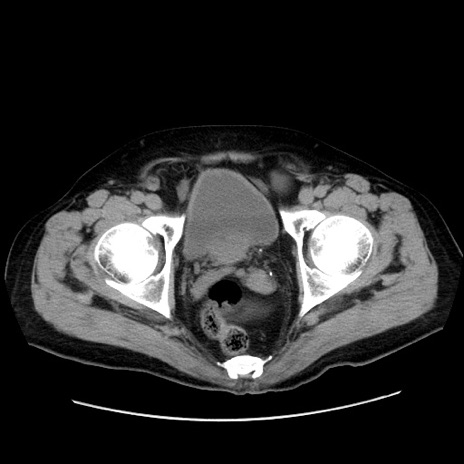

症例30(横断像)

【症例】80歳代男性

【主訴】臍周囲痛

【現病歴】約6時間前から臍下部痛が出現。次第に腹部膨隆・背部痛も生じてきたため来院。背部痛の場所は変化しない。

【身体所見】意識清明、BT 36.3℃、BP  131/87mmHg、P 87bpm、SpO2 100%(RA)、臍周囲自発痛・圧痛あり、反跳痛なし、自発痛部位に一致して板状硬あり、腹部膨隆、腸雑音減弱、CVA tenderness両側陰性。